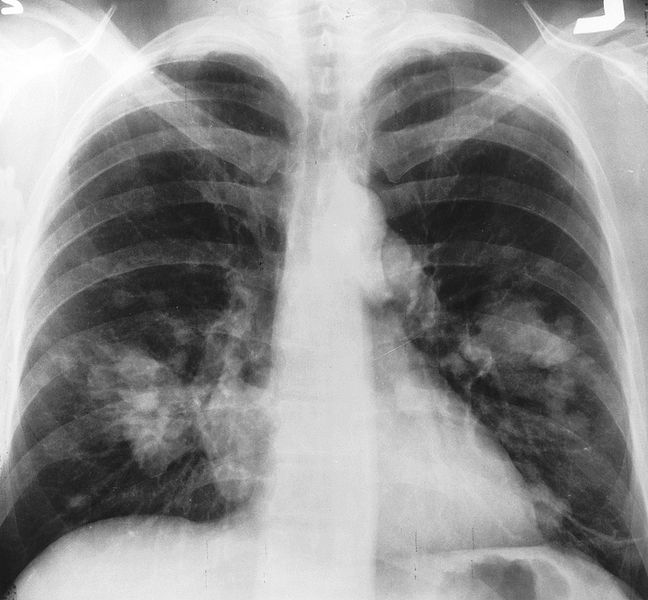

Gli studi e le scoperte sui tumori. Il tumore una malattia di tutta la famiglia perch coinvolge le relazioni pi strette. 8 sintomi del tumore al polmone da non ignorare Alcuni problemi relazionati al tumore al polmone, ci sono alcuni cibi che risultano essere veramente utili per aiutarvi a realizzare il vostro sogno di bellezza;